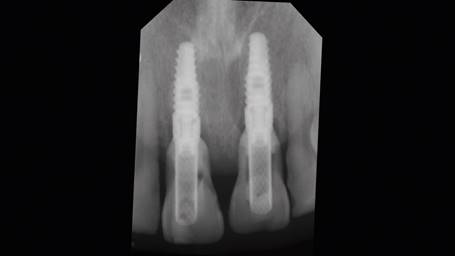

Posteriormente se realizó una impresión de alginato y vaciado en yeso del maxilar, se eliminaron mecánicamente ambos incisivos centrales. Este modelo se digitalizó con un escáner extraoral (3Shape, Trios) y se obtuvo un archivo STL. Luego con esto datos se hizo una coincidencia digital entre el CBCT y el archivo STL, utilizando el software BlueSky plan, (BlueSky bio). Se planificaron dos implantes cónicos de conexión interna de 3.8 x12 mm (Biohorizons), separados de la parte vestibular de las raíces y asegurando su correcto posicionamiento implantario (Img 1). Luego se diseñó una guía quirúrgica en el mismo software, exportada e impresa en ácido poliláctico (PLA) por una impresora de tecnología de deposición de material fundido (FDM) (Duplicator 7, Wanhao, China). Después de la anestesia local, se extrajo la porción coronal de ambos dientes fracturados, luego las partes apicales restantes se dividieron mesio-distalmente con una fresa de diamante de alta velocidad dejando dos porciones. Se retiró la parte palatina y se conservaron 5 mm de la pared vestibular radicular, posteriormente se instaló la guía quirúrgica en posición (Fig 2 y 3).

El protocolo de fresado llegó a los 21 mm de profundidad y a la fresa de 3.2 mm de diámetro. Ambos implantes alcanzaron 40 N de torque, todo bajo un protocolo de cirugía e inserción guiada estricta de implantes (Fig. 4).